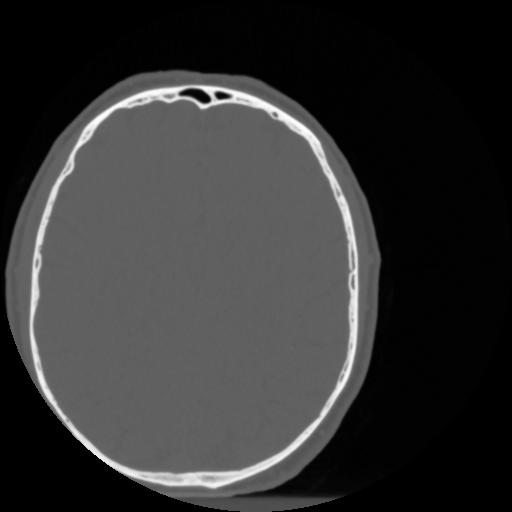

4 CEREBRO,,Vol,0.5,CEREBRO,,